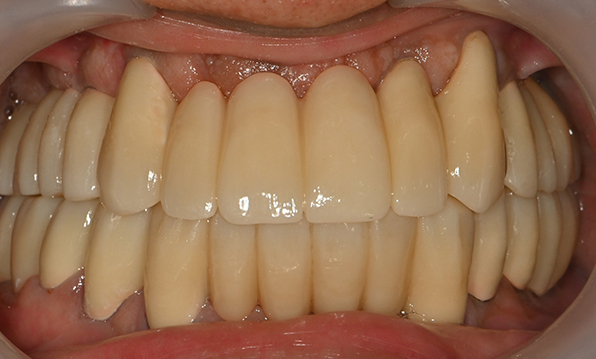

Case 02

Before After